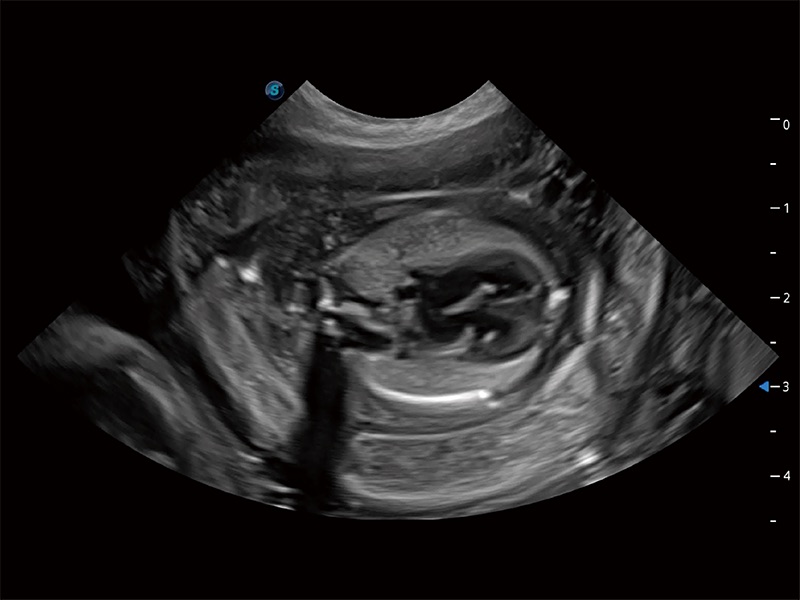

动物是人类最亲密的朋友和最值得信赖的伙伴。云顶集团官网也一直致力于探索动物专用的超声影像解决方案。全新推出的ProPet系列,是云顶集团官网在动物超声影像智能化、专业化、精准化的一次跨越式革新。动物不能用言语来表述自己的不适,通过超声影像,ProPet系列搭建了动物医生与不同物种沟通的“桥梁”,为动物医生注入了“治愈之力”。 ProPet 80 是云顶集团官网匠心打造的一款高端动物专用彩超,采用性能卓越的全新硬件架构,极大提升超声系统的运行效率和数据处理能力,帮助动物医生从容应对日益增多的挑战性病例和日益多样化的临床需求。

高性能和先进的临床应用工具可以为动物医生提供临床信心。ProPet 80 搭载了先进的腹部和浅表应用工具,帮助医生在日常临床实践中发挥前所未有的作用。

ProPet 80 专为动物医生设计,对不同的动物体型和生理结构作出了针对性的优化。通过动物影像专用软件,可满足个性化的应用需求,帮助动物医生获得更精确的诊断数据。

ProPet 80 全新的动物超声智能软件和丰富的探头群,为动物医生提供了高清晰度和精细分辨率的图像,无论在宠物、马科、畜牧还是实验室动物等应用中都可以轻松应对,为您的日常工作带来满意的体验。